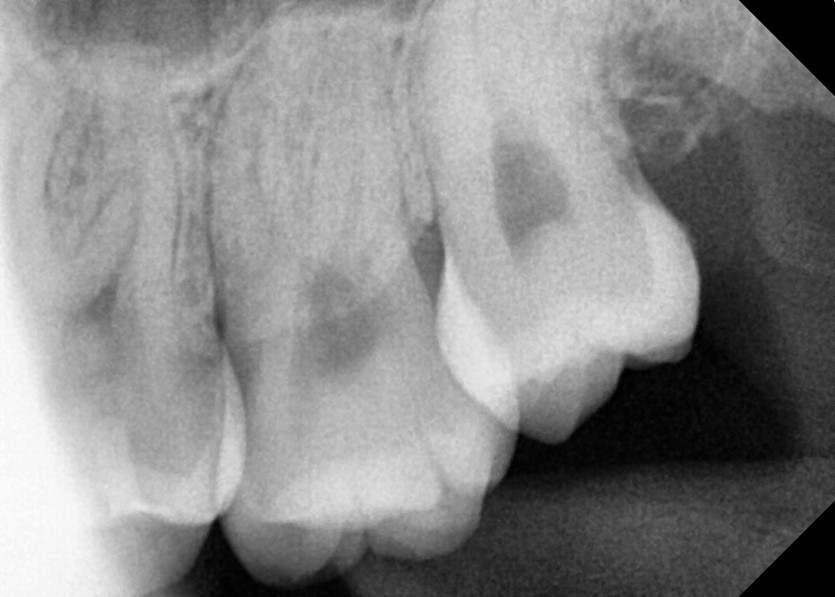

#28,38 사랑니 발치

구강외과 전문의가 당일 발치했습니다.